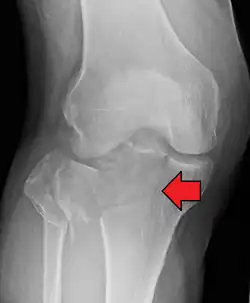

Fractures of the tibial plateau are caused by a varus (inwardly angulating) or valgus (outwardly angulating) force combined with axial loading or weight bearing on knee. The classically described situation in which this occurs is from a car striking a pedestrian's fixed knee (bumper fracture). A bumper fracture is usually a fracture of the lateral tibial plateau, caused by a forced valgus movement. This causes the lateral part of the distal femur and the lateral tibial plateau to come into contact, compressing the tibial plateau and causing the tibia to fracture. The name of the injury is because it was described as being caused by the impact of a car bumper on the lateral side of the knee while the foot is planted on the ground, although this mechanism is only seen in about 25% of tibial plateau fractures.[5] The term "bumper fracture" was coined in 1929 by Cotton and Berg.[6] Fracture of the neck of the fibula may also be found, and associated injury to the medial collateral ligament or cruciate ligaments occurs in about 10% of cases.[7][8]

However, most of these fractures occur from motor vehicle accidents or falls. Injury can be due to a fall from height in which knee forced into valgus or varus. The tibial condyle is crushed or split by the opposing femoral condyle, which remains intact. The knee anatomy provides insight into predicting why certain fracture patterns occur more often than others. The medial plateau is larger and significantly stronger than the lateral plateau. Also, there is a natural valgus or outward angulation alignment to the limb which coupled with the often valgus or outwardly angulating force on impact will injure the lateral side. This explains how 60% of plateau fractures involve the lateral plateau, 15% medial plateau, 25% bicondylar lesions. Partial or complete ligamentous ruptures occur in 15-45%, meniscal lesions in about 5-37% of all tibial plateau fractures.[9]